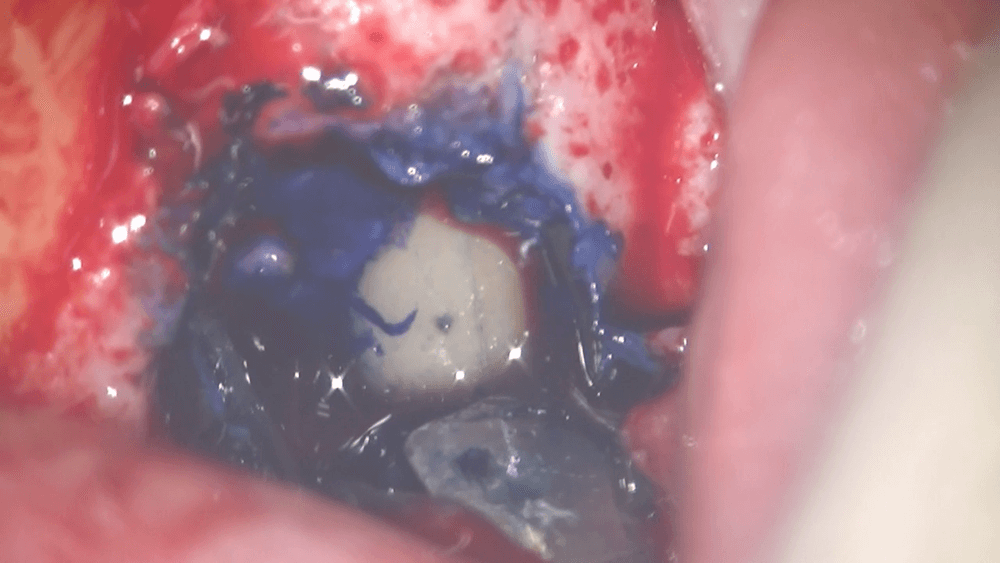

歯茎を切開し、根の状況を確認しました

ここで問題なのが、その汚れが、どのような原因でこびりついているのか?です。これには、大きく3つの問題がありますが、今回のケースでは、根の先にまだ汚れがついているのか、はたまた、根にヒビが入り、そのヒビの間に入り込んだ汚れが悪さをしているのか、どちらかが強く疑われました。そのため、患者さんと相談し、歯茎を切開し、根の表面をマイクロスコープで確認することになりました。

歯茎を切開し、

根の表面をマイクロスコープで確認すると、ヒビが入っていました。

⭕️で囲みました。このような場合は、基本的に抜歯なります。歯茎の腫れの原因は、根の表面に入ったヒビに入り込んだ汚れであり、その汚れを、抜歯という外科的処置にて取り除く、ということになります。